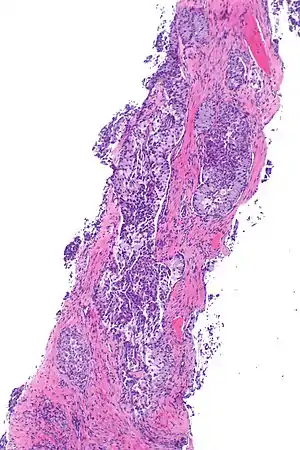

| Micrograph showing ALK positive lung adenocarcinoma. H&E stain. | |

Most lung carcinomas containing the EML4-ALK gene fusion are adenocarcinomas.

Some studies suggest that the papillary adenocarcinoma and the signet ring cell adenocarcinoma[3] variants are more likely to carry this fused gene than other histological variants.